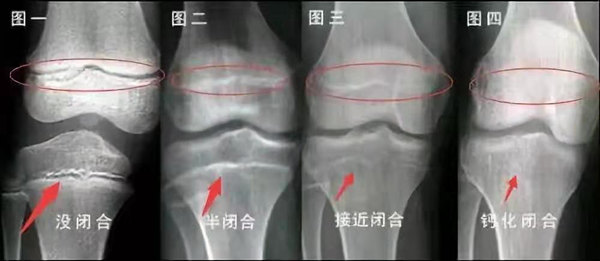

我們都知道,人體的高矮是由骨骼的生長發(fā)育決定的,特別是下肢長骨。長骨呈長管狀,在長骨的兩端有一種專管骨骼生長的骺軟骨,它與干骺端之間有一盤狀軟骨結構稱為骺板(線),在幼兒的X光片上表現(xiàn)為一條較寬的透光帶。 (見下圖)

未成年時隨著年齡的增加骺軟骨端不斷骨化,骨骼就不斷增長。當骨骺線完全閉合時骨骼就停止生長,個子也就不再增長了。一般骨骺端完全閉合的年齡是18~20歲左右。

骨骺線提前閉合最多見的情況是性早熟,而這也是很多醫(yī)生專家建議孩子進行骨齡測量的原因之一。另外,在兒童時期大量補鈣也會使骨骺端提前過早閉合。

一般來說,女孩的骨齡超過14歲,男孩的骨齡超過16歲,這時其骨骺線已接近閉合,基本沒有長高的機會了。

因此,越早了解骨骺線閉合情況,越早干預,孩子長高的可能性越大。